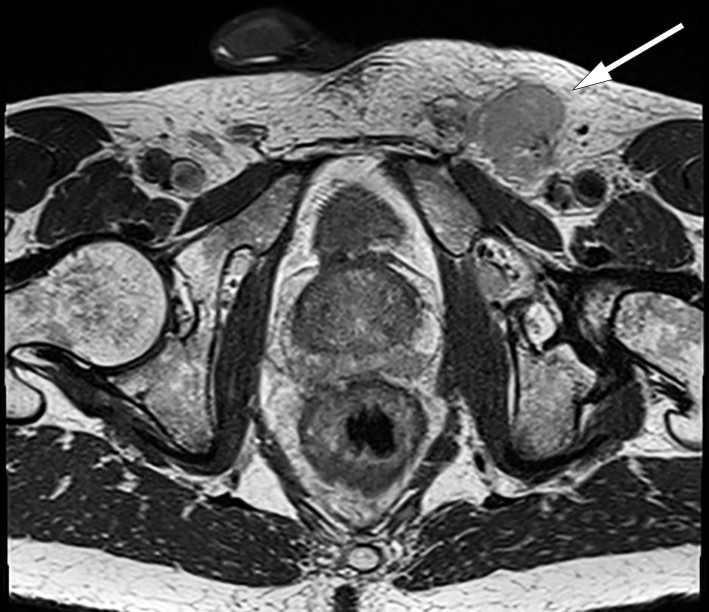

Videre utredning viste normale orienterende blodprøver, inklusive CEA på 1,3 mcg/L (˂ 5,0). To dager etter første kontakt ble pasienten koloskopert med normale funn, foruten de kjente forandringene i nedre analkanal. Histologiske svar på biopsier forelå etter en uke. Biopsier fra rektum viste rektumslimhinne med intestinal spiroketose uten tegn til malignitet. Biopsier fra perianal tumor viste kronisk aktiv plasmacellerik inflammasjon uten tegn til malignitet. Etter ti dager ble det utført MR bekken som viste en malignitetssuspekt tumor på 1,6 × 0,7 × 3,5 cm kl. 12–3 i nedre del av analkanalen med mulig affeksjon av intern analsfinkter (figur 1). I tillegg ble det påvist flere forstørrede lymfeknuter langs arteria og vena iliaca communis på venstre side, i mesorektum og i venstre lyske (figur 2). Den største lymfeknuten i venstre lyske ble målt til 2,0 × 5,4 cm. CT thorax/abdomen/bekken viste forstørrede lymfeknuter langs arteria og vena iliaca communis på venstre side og paraaortalt, men ingen andre tegn til metastaser.

Inflammasjon i rektum kan føre til fortykkelse av tarmveggen som kan gi et tumoraktig utseende, og kan være ledsaget av uttalt lymfadenopati (8). Det er publisert flere kasuistikker hvor lymphogranuloma venereum ble tolket som malign tilstand. Radiologisk kan det være svært vanskelig å skille mellom lymphogranuloma venereum og malignitet som adenocarcinom, lymfom, og lymfeknutemetastaser. Noen ganger kan symptomer og endoskopiske funn ligne på inflammatorisk tarmsykdom (13). Differensialdiagnoser inkluderer derfor infeksiøse, inflammatoriske, iskemiske og neoplastiske prosesser (8, 13).